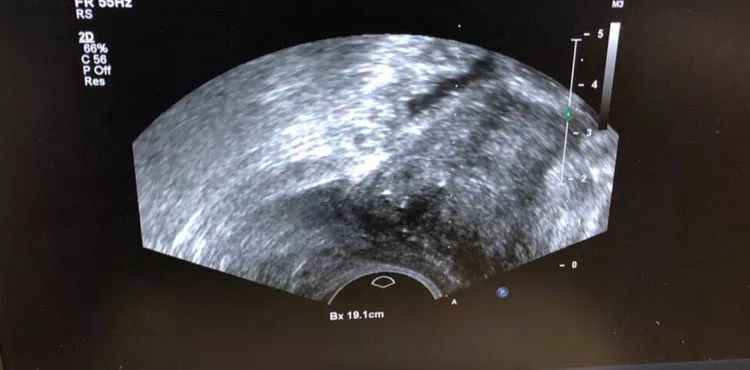

近日,我院泌尿外科与超声诊断科联合完成了两例超声介入引导下前列腺穿刺活检术。

为完成此次合作,泌尿外科副主任医师王宜林,张跃曦,超声医学科主治医师杜轲峰,住院医师崔斌预先完成了诊室全方位消毒及仪器调节、穿刺引导线校正,穿刺引导架消毒,两科室通力合作,历时两个小时,成功完成了首次超声引导下前列腺穿刺活检术。

超声介入技术作为现代超声医学的一个分支,它是在超声显像基础上为进一步满足临床诊断和治疗的需要而发展起来的一门新技术。该技术通过超声引导可动态观察穿刺针进入病灶的情况,实时显示穿刺的全过程,准确地完成各种穿刺活检以及抽吸、插管、注药治疗等操作,具有操作精准,成功率高,并发症少等优点,是一项安全可靠的临床治疗技术,有很高的临床应用价值。此次超声引导下前列腺穿刺活检术的成功开展,是超声诊断科与泌尿外科跨学科协作的结果,标志着医院在此项技术的应用方面走在了全市及周边地市的前列。